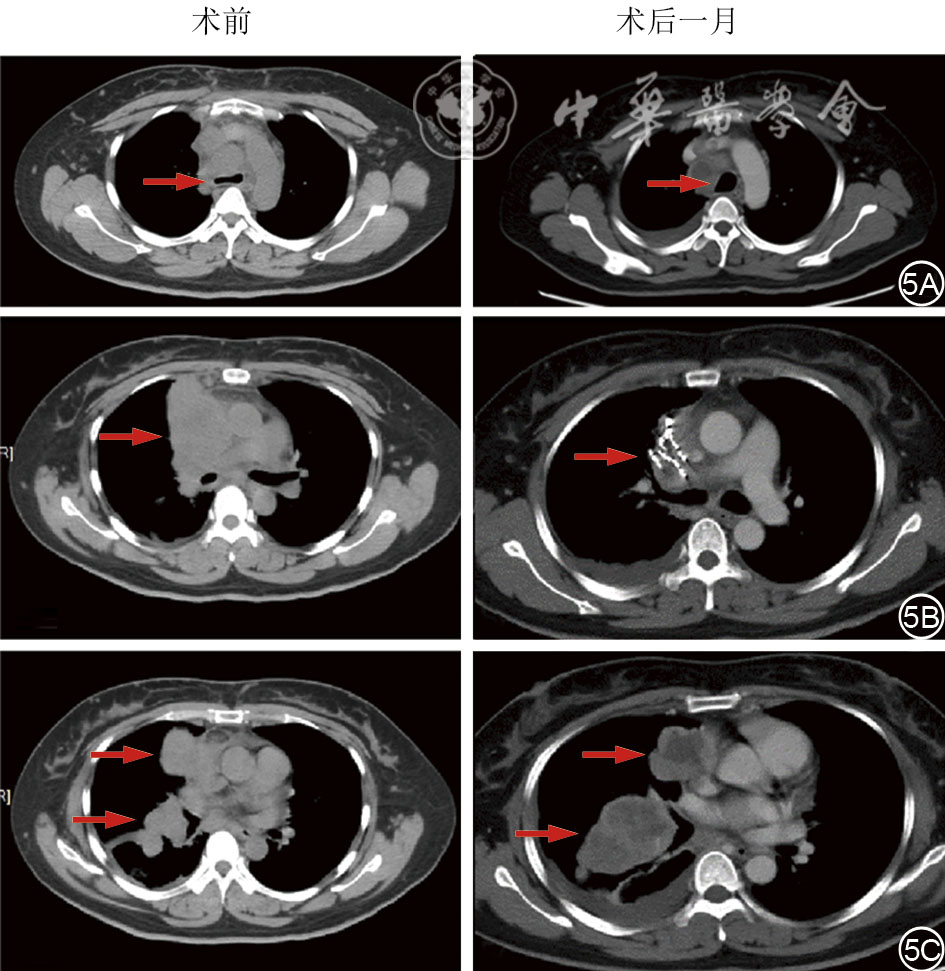

We present a case of a 40-year-old female patient with midline carcinoma, who was admitted for chest pain and cough and diagnosed with concurrent mediastinal and pulmonary metastases. Single-agent chemotherapy proved ineffective and her clinical symptoms aggravated, accompanied by tracheal and superior vena cava compression. Following multidisciplinary consultation, CT-guided 125Ⅰ seed implantation was initially performed. Local tumors regressed postoperatively while partial pulmonary metastatic lesions progressed, prompting seed reimplantation combined with bronchial arterial chemoembolization, followed by concurrent anlotinib targeted therapy and sintilimab immunotherapy. After six months of comprehensive treatment, the thoracic tumors resolved, lymph nodes shrank, radiological evaluation indicated partial response, and the patient's clinical symptoms were significantly relieved. This case demonstrates that the integrated regimen of interventional local therapy plus targeted and immunotherapy offers a viable therapeutic approach for inoperable midline carcinoma patients with refractory conventional chemotherapy, enabling rapid symptom relief and improved treatment efficacy.